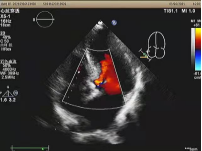

瓣膜完全释放,无瓣周漏

在多学科协作下,蚌埠市第二人民医院成功完成了首例TAVR手术,术后患者冠脉血流通畅,跨瓣压差改善明显,手术取得圆满成功。与传统开胸体外循环下主动脉瓣置换术相比,TAVR手术避免了开胸、体外循环、心脏停跳等危险因素,大大降低了手术风险,具有创伤小、恢复快、痛苦低、住院时间短等优势。对于高龄且无法耐受开胸手术,以及外科手术高危极高危的患者来说,无异于希望之光。蚌埠市第二人民医院此项手术的成功开展也填补了蚌埠市市级医院在该领域的空白,将为市域及周边地区的主动脉瓣膜病患者带来福音。